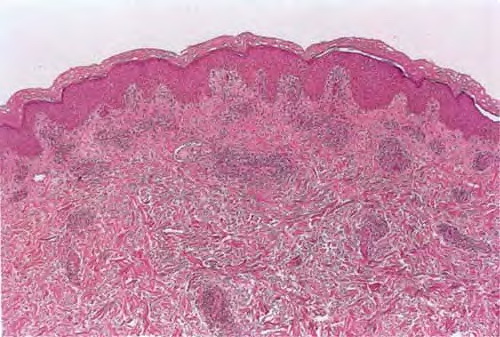

Atlas of skin histopathology

Mucha-Habermann disease = داء موشاهابرمان